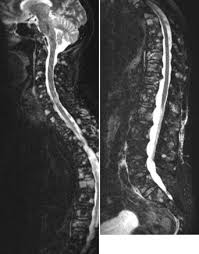

3 Radiologische Diagnostik Des Multiplen Myeloms 3 3 Radiologisch Pathologische Korrelation